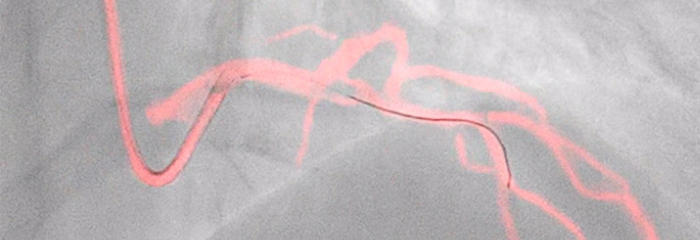

See clearly, guide confidently — Dynamic Coronary Roadmap

Automatic, real-time navigational guidance designed for procedure efficiency in complex PCI interventions without changing current standard workflow.You are about to visit a Philips global content page

Dynamic Coronary Roadmap

Dynamic Coronary Roadmap, a Philips-exclusive technology, creates a motion-compensated, real-time view of coronary arteries. Recent evidence demonstrates that DCR can reduce contrast agent by 28.8% during a PCI procedure. With DCR a highlighted coronary angiogram is superimposed on a live 2D fluoroscopic image, creating a colored roadmap that adjusts automatically, providing continuous visual feedback on positioning of wires and catheters.